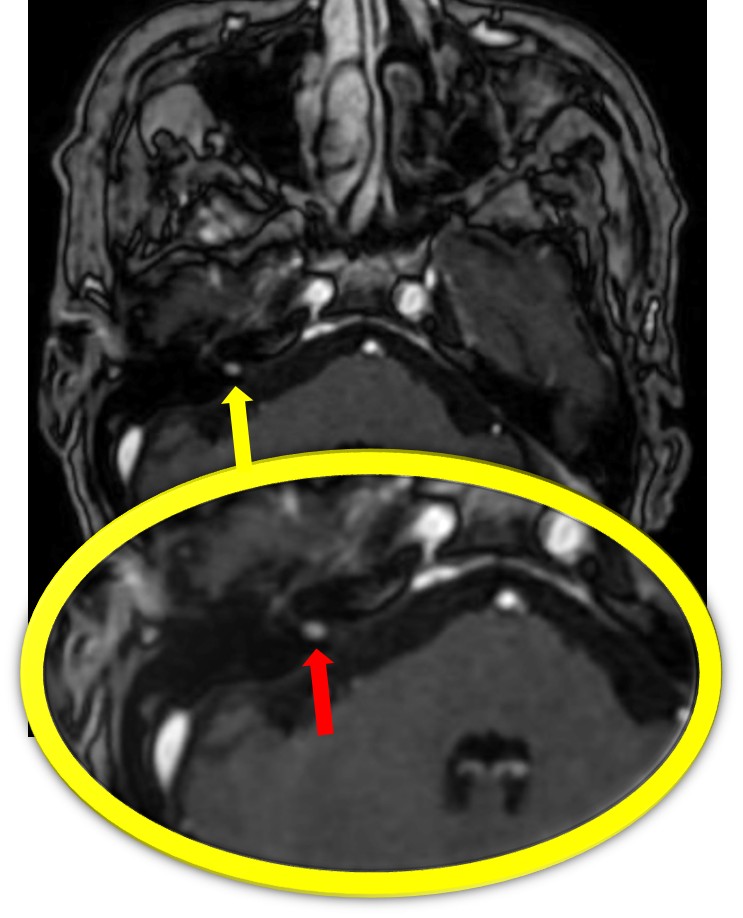

FIESTA同様、微小な腫瘍が白く(高信号)として描出